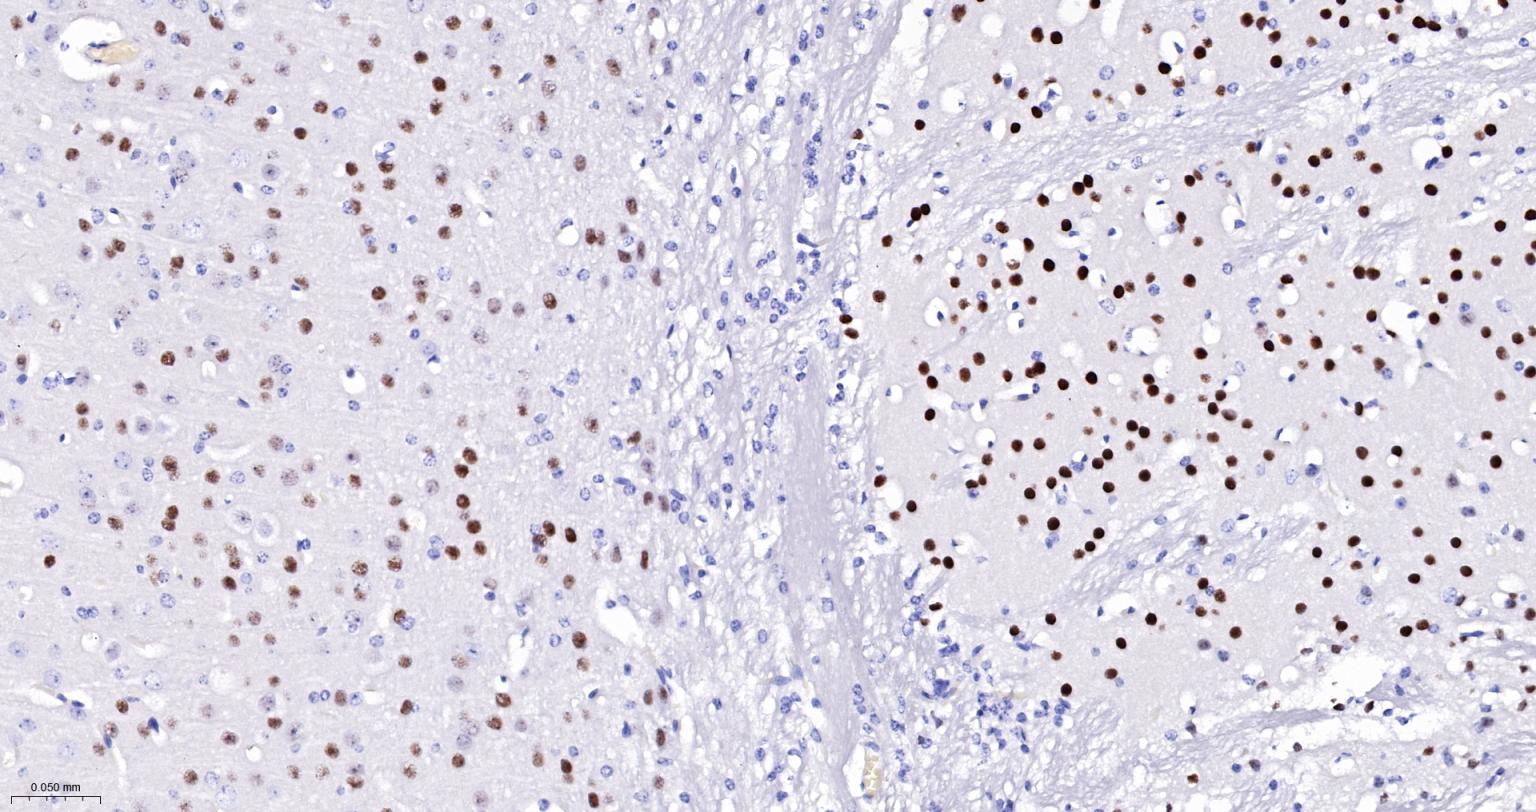

Paraformaldehyde-fixed, paraffin embedded Mouse Cerebrum; Antigen retrieval by boiling in sodium citrate buffer (pH6.0) for 15 min; The section was incubated with Ctip2 Monoclonal Antibody, Unconjugated (bsm-61400R) at 1:200 overnight at 4°C, followed by conjugation to the bs-0295G-HRP and DAB (C-0010) staining.